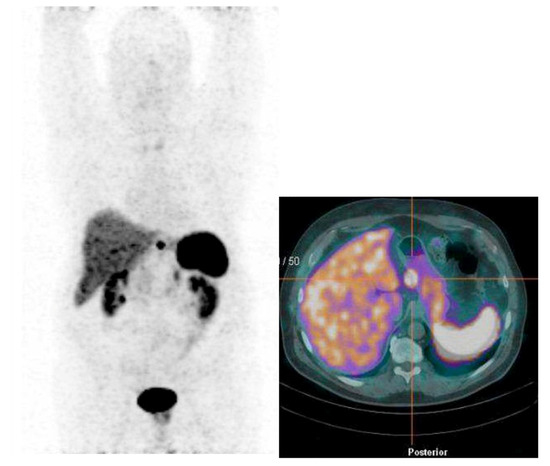

| Patient 7 | 20 mm | 3% | No | Yes | No | No | Yes | Yes | No |

| Patient 8 | 20 mm | 2% | No | Yes | No | No | Yes | Yes | No |